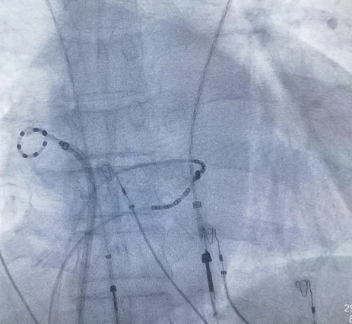

泛血管疾病管理中心高水准完成

脉冲电场消融手术

2025年8月,泛血管疾病管理中心高水准完成脉冲电场消融(PFA)手术,引领心律失常治疗新趋势。这项技术为心律失常患者提供了更安全、更有效的治疗方案,标志着医院在心血管介入领域的技术突破。